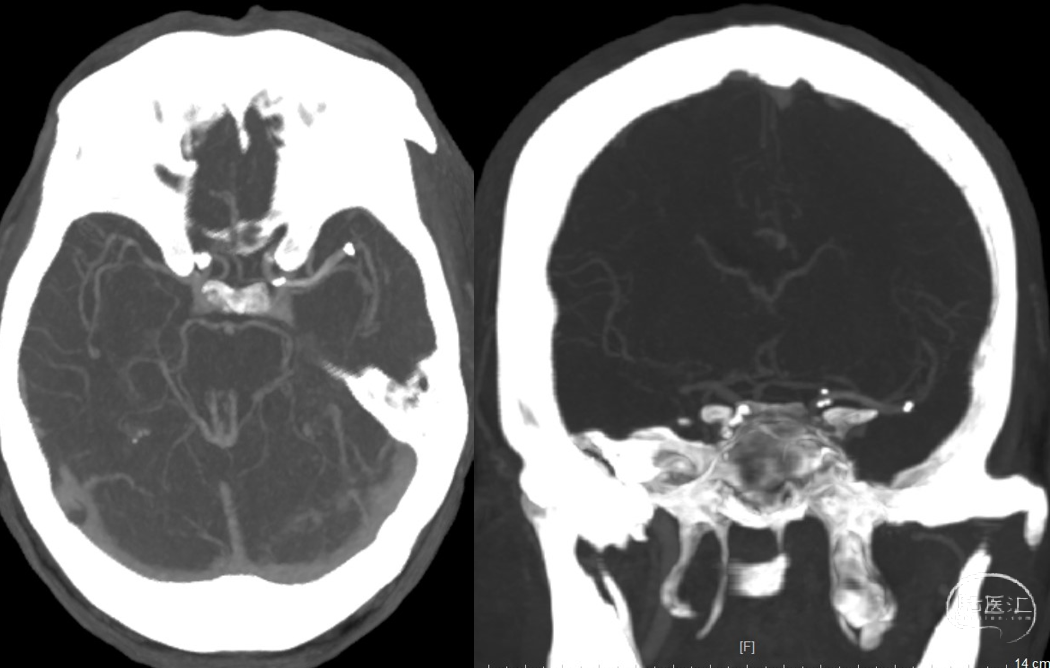

急诊头颅CT:未见明显新发梗塞(2021-12-21)

头颅CTA:左侧M1以远闭塞

2021-12-21 头颅CTA、颈部CTA:

1、左侧大脑中动脉M1以外闭塞。右侧M2段局部变细明显,不除外发育异常,余大脑动脉符合动脉粥样硬化改变。